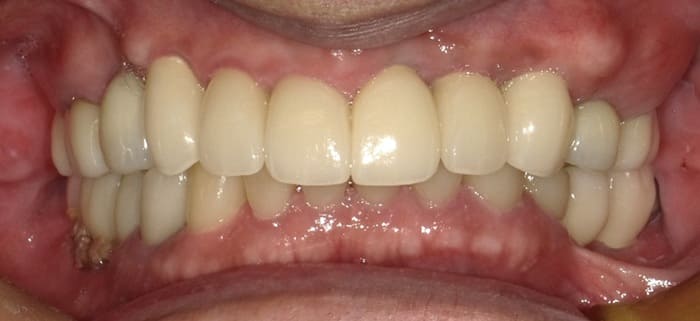

上顎インプラント埋入手術後4ヶ月でインプラント体と骨の結合を確認して両側上下顎臼歯部のインプラントに上部構造(歯の部分)を装着した。

臼歯部のVertical Stopを確保した上で上顎前歯部のインプラント埋入手術を行った。

上顎前歯部インプラント埋入を行った後3ヶ月で前歯部のインプラントの歯の部分を装着するための印象、咬合採得と温存できた#13,12,21への歯冠補綴を行った(歯科技工士さん立ち会い)。

上顎前歯部と両側小臼歯部はインプラント補綴を行い、両側の大臼歯部についても根管治療からやり直して咬合平面を改善すべく補綴を行った。下顎の両側臼歯部に関してもインプラント補綴を行い小臼歯部では根管治療からクラウンによる補綴を行った。左上7番に関しては当初インプラント補綴を行う予定であったがサイナスリフトを伴う治療になることと第一大臼歯までで十分噛めることから埋入せずに経過を見ている。

治療後の口腔内所見である噛み合わせも問題なく機能している。また、一本ずつのインプラント補綴を行ったことでフロスによるケアができ良好な口腔内環境を維持できている。